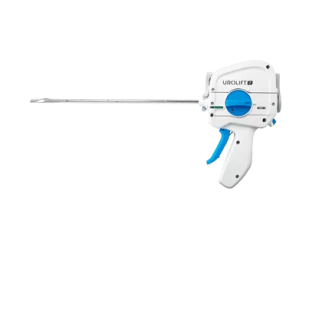

장비 소개

프로게이터 (2세대 전립선 결찰술)

프로게이터 (2세대 전립선 결찰술) -